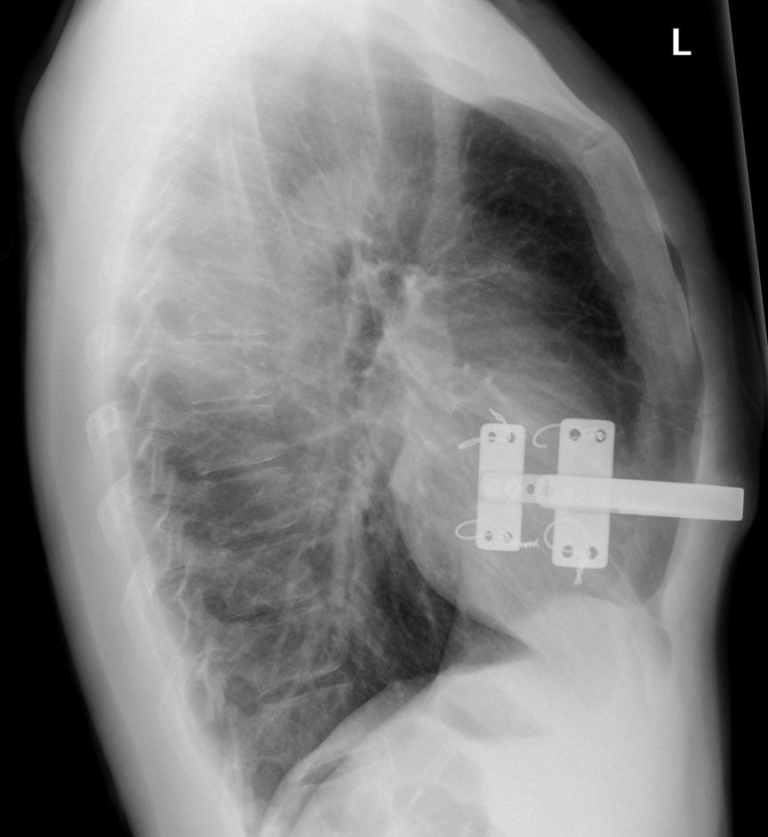

Pigeon Chest X Ray Pigeon Chest Correction Pectus carinatum is a condition that makes your breastbone stick out beyond where it should. How is pectus carinatum (pigeon chest) treated? Pectus carinatum, or pigeon chest, causes the sternum, or breastbone, to protrude out in front of the rest of the chest. While the condition may cause only minor physical issues, it can. Pectus carinatum or pigeon chest, is. Pigeon Chest Correction.